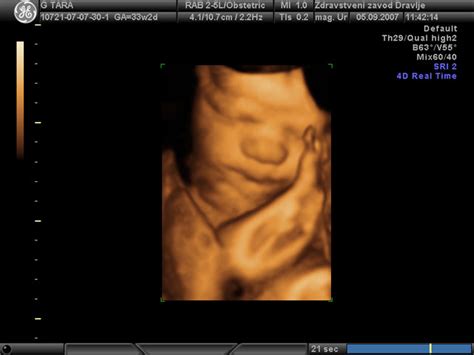

Že dolgo je znano, da nosečnost ne predstavlja povečanega tveganja za nastanek multiple skleroze. Tveganje za nastanek multiple skleroze med nosečnostjo je v primerjavi z obdobjem po porodu manjše, vendar pa je tveganje za nastanek multiple skleroze pri ženskah, ki nikoli ne rodijo, večje, kot je pri ženskah, ki imajo najmanj tri otroke. V evropski multicentrični raziskavi PRIMS so še dve leti po porodu spremljali 227 žensk. Ugotovili so, da se med nosečnostjo zmanjša število zagonov bolezni; ta upad je najizrazitejši v zadnjem trimestru. Verjetnost za ponovni zagon bolezni pa se močno zveča zlasti v prvih treh mesecih po porodu. Kot zagotavlja dr. Alenka Horvat Ledinek, multipla skleroza ne vpliva na nosečnost. Pri svojem delu se večkrat srečuje z željo bolnic po tem, da bi imele otroka. Kaj jim svetuje? "Najprej jim svetujemo, da se za načrtovanje nosečnosti odločijo v obdobju, ko je bolezen stabilna, ko ni zagonov bolezni in bolnica že nekaj let prejema terapijo z enim od zdravil, ki upočasnjujejo bolezenski proces. Zadržkov ni, kadar bolnica prejema zdravila prvega reda, kot glatiramer acetat in IFN-beta-1a subkutano ter IFN-beta-1b subkutano: zdravljenje s temi se lahko nadaljuje tudi med nosečnostjo. Na srečo nosečnost sama upočasni vnetni proces in zmanjša tveganje za zagon bolezni. Vsekakor pa je potrebna velika previdnost tudi pri skupini zdravil, ki jih zdravnik predpiše za obvladovanje različnih težav, kot so npr. utrudljivost, mokrenje, krči. Raziskave so celo pokazale, da se število zagonov bolezni med nosečnostjo zmanjša, še posebej v zadnjem trimesečju. Pri bolnicah z MS so zelo pogoste okužbe sečil, še posebej v času nosečnosti. Tudi v času nosečnosti pa lahko pride do zagona bolezni. V tem primeru je potreben posvet med nevrologom in ginekologom porodničarjem glede zdravljenja z infuzijami kortikosteroidov. Porod naj bo po naravni poti, če seveda ni medicinskih zadržkov. Zelo pomembno je obvladovanje bolečine in zato pride prav posvet z anesteziologom. Različne oblike lokalne anestezije ne predstavljajo pri bolnicah z MS nobene ovire. Nemalokrat lahko prav s spinalno anestezijo zmanjšamo krče v nogah in olajšamo porod v zadnji, iztisni fazi. Dokazano je, da bolnice z multiplo sklerozo nimajo večjega števila spontanih splavov kakor zdrave ženske, prav tako ni poškodb pri novorojenčkih. Tudi nosečnost sama ni bolj rizična, poteka tako kot pri zdravi ženski.

Bolnica z multiplo sklerozo lahko rodi po naravni poti. Odločitev o načinu poroda je v rokah porodničarja. Bolnice nekoliko pogosteje rodijo s carskim rezom. Pri porodu po naravni poti večkrat potrebujejo pomoč z vakuumom v primerjavi z zdravimi ženskami, prejmejo lahko anestezijo in/ali epiduralno anestezijo.